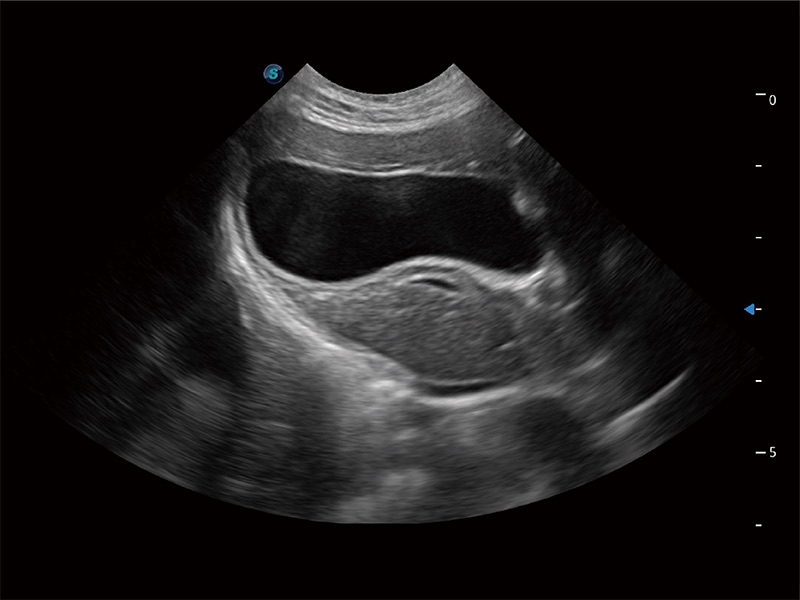

动物是人类最亲密的朋友和最值得信赖的伙伴。环球UG官网也一直致力于探索动物专用的超声影像解决方案。全新推出的ProPet系列,是环球UG官网在动物超声影像智能化、专业化、精准化的一次跨越式革新。动物不能用言语来表述自己的不适,通过超声影像,ProPet系列搭建了动物医生与不同物种沟通的“桥梁”,为动物医生注入了“治愈之力”。 ProPet 80 是环球UG官网匠心打造的一款高端动物专用彩超,采用性能卓越的全新硬件架构,极大提升超声系统的运行效率和数据处理能力,帮助动物医生从容应对日益增多的挑战性病例和日益多样化的临床需求。

高性能和先进的临床应用工具可以为动物医生提供临床信心。ProPet 80 搭载了先进的腹部和浅表应用工具,帮助医生在日常临床实践中发挥前所未有的作用。

ProPet 80 全新的动物超声智能软件和丰富的探头群,为动物医生提供了高清晰度和精细分辨率的图像,无论在宠物、马科、畜牧还是实验室动物等应用中都可以轻松应对,为您的日常工作带来满意的体验。